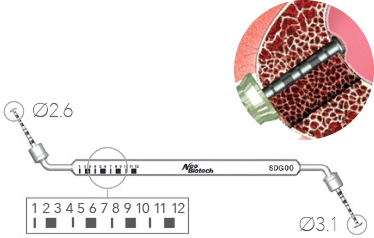

Глубиномер

SADG01